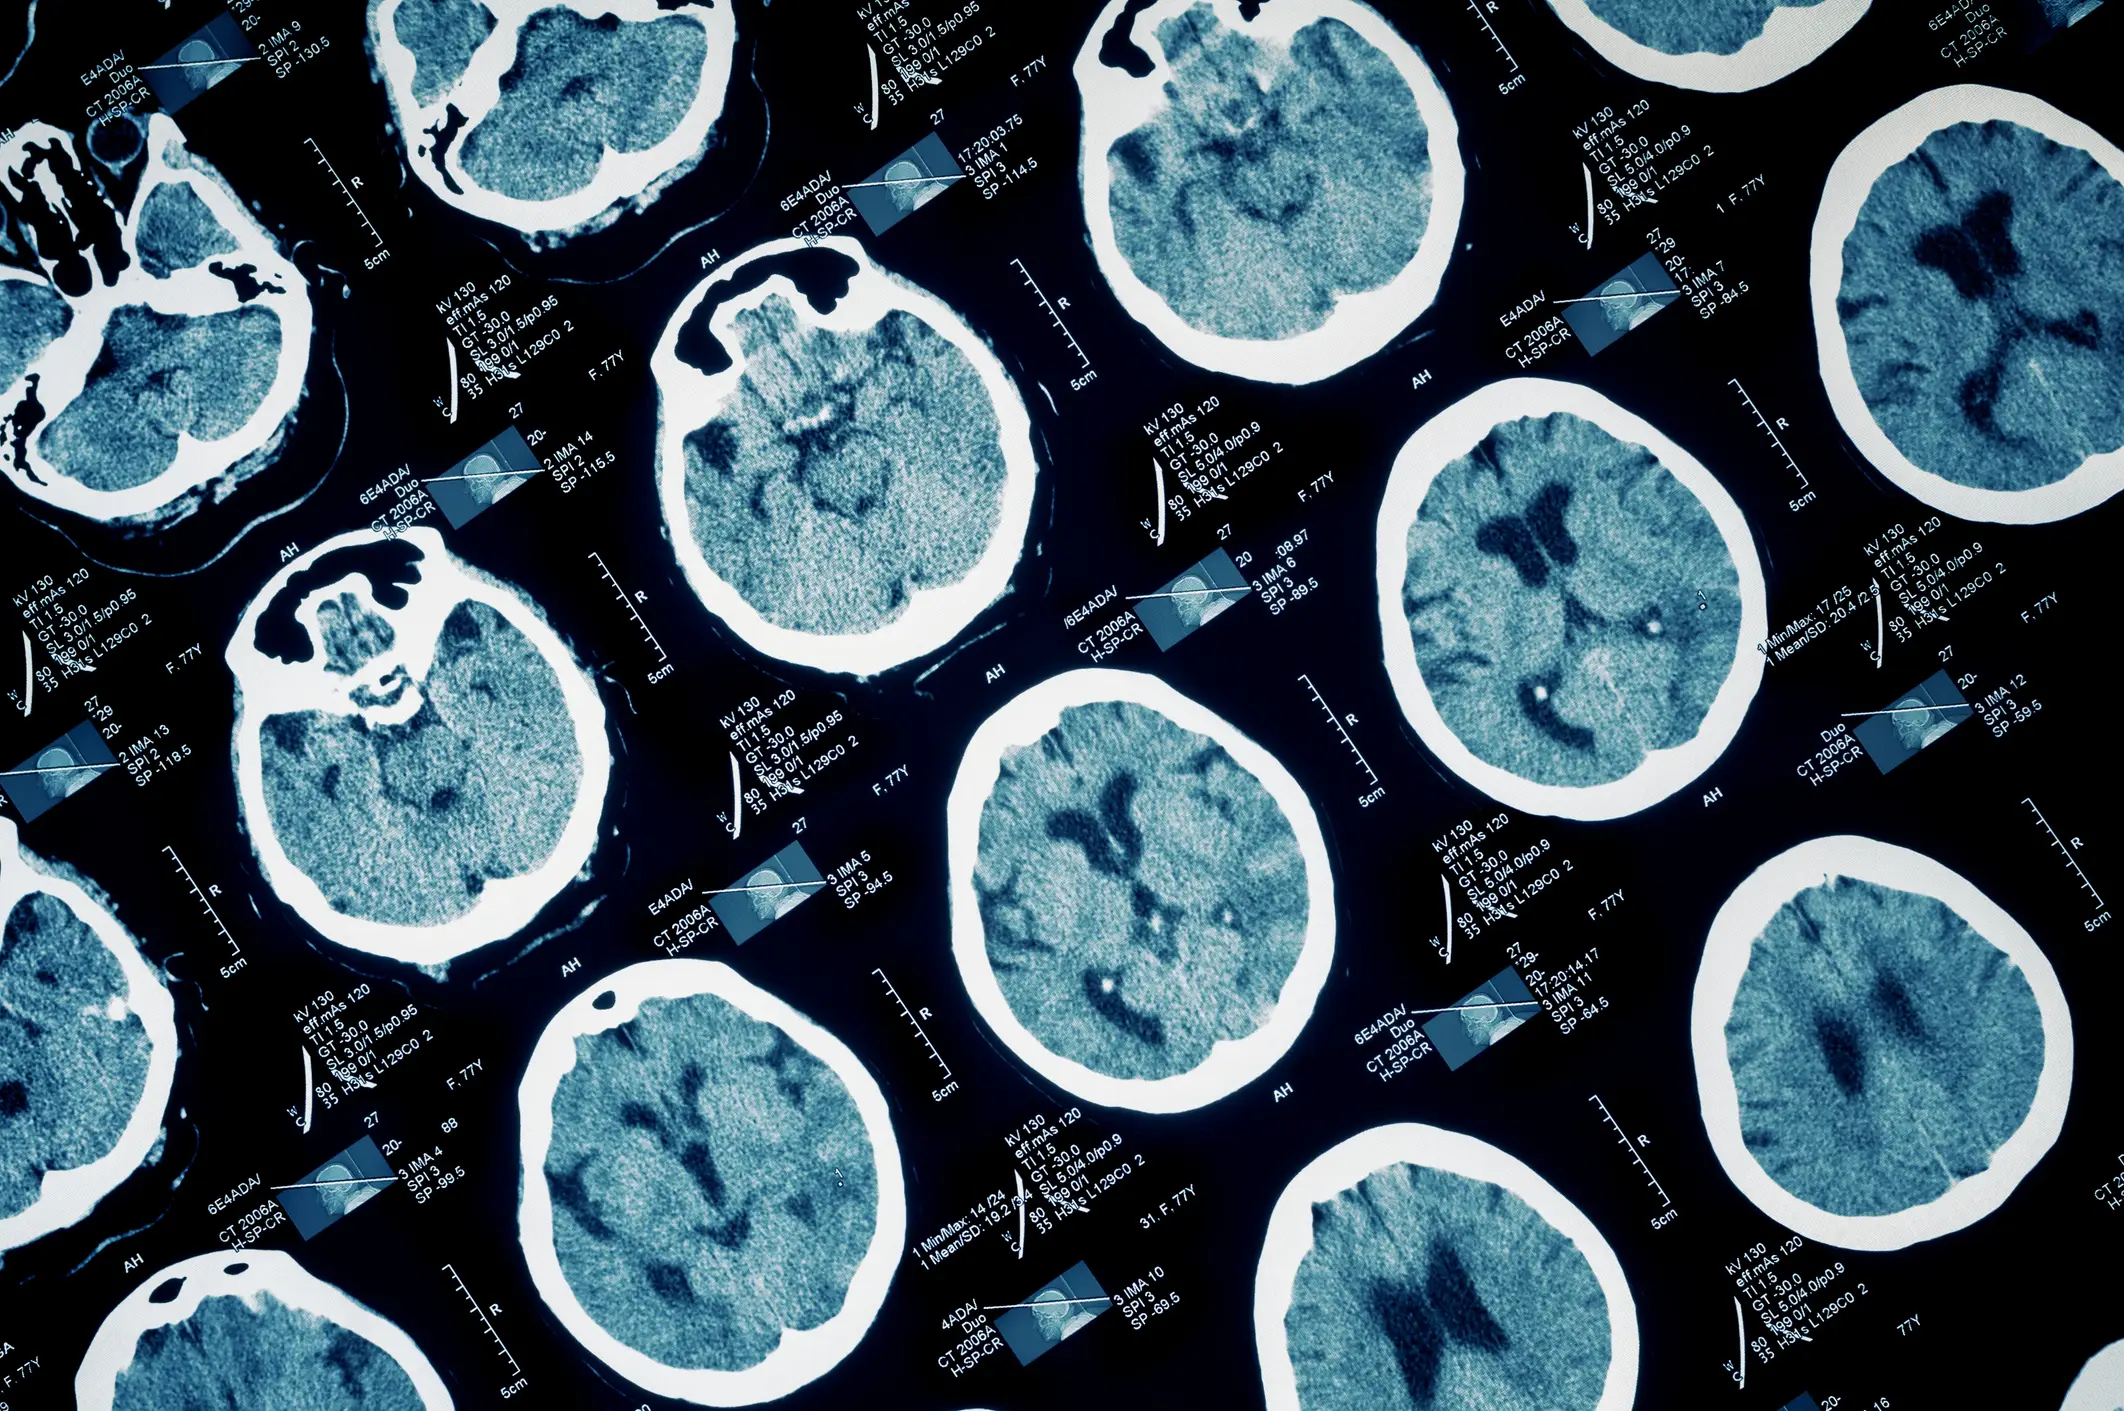

What Is a Traumatic Brain Injury?

A traumatic brain injury (TBI) occurs when an external force, such as a blow, jolt, or penetrating wound, disrupts the normal function of the brain. In Long Beach, where speeding, multiple construction projects, and bustling pedestrian zones are common, TBIs are an unfortunate risk for residents and visitors. These life-altering injuries can range from relatively mild concussions to severe brain trauma requiring around-the-clock medical care. The effects are not only physical but emotional and financial, placing immense strain on both victims and their families.ย

Brain injury litigation presents several unique challenges that require experienced legal representation to navigate effectively. One of the biggest hurdles is proving invisible injuries. Unlike broken bones, brain injuries donโt always appear on X-rays or standard medical imaging. Insurance companies often use this to their advantage, arguing that the victimโs symptoms are exaggerated, unrelated to the accident, or caused by preexisting conditions. An experienced attorney will work closely with neurologists, neuropsychologists, and radiologists who can provide more advanced diagnostics, like fMRI scans or neurocognitive testing, to establish the injury and its severity.